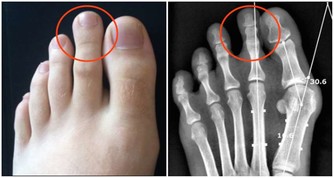

有的人早上起來不停吐痰,沒完沒了,這就說明有痰毒了。痰毒一般由飲食而來,或因肺功能不好導致。如果氣管不好,痰多,可以喝二陳湯來治癒,可服茯苓、半夏、陳皮各10克,甘草6克,用水煮了喝,喝上7天痰即可化。日常飲食上,蘿蔔是最好的化痰食物,可以買生蘿蔔加點香醋涼拌吃;另外還可以多吃冬瓜、無花果、紫菜、羅漢果等清熱化痰之品。 4、脂毒

有脂毒的人一般偏胖、脂肪較多,經常喝酒、吃肉、吃油炸食品,對肝臟傷害很大,易得脂肪肝等疾病。想清除脂毒,首先要降血脂,建議用山楂、荷葉煮水喝,可化痰降脂;平時應多吃洋蔥等蔬菜;還可按揉小腿上的豐隆穴(位於外踝尖上8寸,條口穴外,距脛骨前緣二橫指處),可以消食導滯,減少脂肪。 5、瘀毒 瘀毒是指藏在血液里的毒,大多是從中年開始出現的,一般表現為舌下脈絡發紫、容易健忘、皮膚乾燥、胸悶憋氣、臉色暗等。有瘀毒的人,也可以用丹參或山楂泡水喝,可以活血化瘀,清除血管垃圾。 6、氣毒 氣毒是存在肺裡面的毒,中醫認為「肺主氣」、「腎主納氣」,有氣毒的人往往肺腎功能不好,一般身上氣味大,如有口臭、汗臭等。為了防止氣毒,可以每天早起做深呼吸,即「呼吸吐納」,把肺中的濁氣排出來,保持體內空氣的新鮮。

值得提出的是,肝是人體最大的排毒工廠,想要祛除毒素,要從根本上保肝養肝,使之能解毒排毒。建議經常用枸杞、菊花泡水喝,多吃桑葚,以及各類新鮮蔬菜。 日常生活中如何排毒 可別小瞧了這六種陰毒,如果這些毒素在我們的體內越積越多,那麼就會引起各種身體疾病,加速人的衰老。肝臟、腎臟和肺部是身體中最大的解毒器官,要想徹底排出身體的毒素,必須要保養好這些器官。除了上述排毒方法,在日常生活中應該如何排毒呢? 1、定時排便 便秘的滋味確實不好受,長期便秘也會讓我們的腸道積累大量的毒素,引起各種身體疾病。生活中我們除了要注意健康均衡的飲食外,還要養成定時排便的好習慣。無論身體有沒有便意,早上起床後都可以到馬桶上坐一會兒,培養自己的便意。時間長了,這樣就可以養成晨起排便的習慣。 想要定時排便,還可以按摩身體上的「排便穴」。這個穴位位於食指關節的尺側凹陷處,只要按摩一兩分鐘,身體就會產生強烈的便意。 2、堅持運動 現在很多人每天都忙於工作和應酬,很難抽出時間來運動健身。其實,要是能堅持每天都鍛鍊身體,這樣也可以幫助我們輕鬆排除體內的毒素。 比如:跑步、游泳和瑜伽等等。經常運動可以增強人的心肺功能,還能夠促進體內的血液循環。如果在運動過程中適量地補充一些水分,還可以加速身體排出毒素。 3、多吃素 我們每天都要攝入大量的食物,食物進入腸道後,一般要停留兩三天的時間。如果攝取過多的高糖、高脂肪和高膽固醇的食物,那麼身體就不容易消化,產生宿便。宿便對身體的危害非常大,可以使毒素在腸道中被二次吸收。 要想身體不積累毒素,可以多吃點素,少吃點葷腥。可以在一個星期當中選擇一天專門吃素食,這樣可以幫助我們清理腸胃。平時可以多吃點新鮮的瓜果蔬菜,因為這些食物中富含纖維素,可以促進人的腸胃蠕動,幫助身體把宿便排出去。 4、保持好心情 現在人們的生活節奏越來越快,工作壓力也比較大。如果長期處於精神緊張的狀態,就會影響五臟六腑的正常運行。很多時候我們生病都是因為工作壓力大和精神緊張導致的,因此,大家要放慢生活節奏,保持愉悅輕鬆的心情。 5、不熬夜 都說熬夜就是慢性自殺,熬夜對人體健康的傷害特別大。在晚上,身體的大部分器官都會進行排毒工作。如果晚上不睡覺,那麼排毒器官就會罷工。長期熬夜就會導致分泌系統紊亂,新陳代謝功能出現障礙,身體也會產生各種各樣的毒素。要想徹底排除體內的這些毒素,就要養成良好的作息習慣,保證充足的睡眠,儘量不要熬夜。 健康養生的第一步,讓我們排出毒素開始吧! -